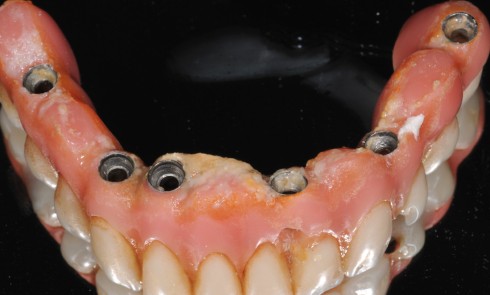

La prothèse scellée Le scellement de restaurations sur des piliers implantaires demeure une solution très intéressante (fig. 1). Cette technique reprend...

Article réservé à nos abonnés La maintenance personnelle et professionnelle dans la prévention de la péri-implantite

Étiopathogénie et facteurs de risques La péri-implantite est une maladie multifactorielle dont l’étiologie principale est constituée par les bactéries contenues...